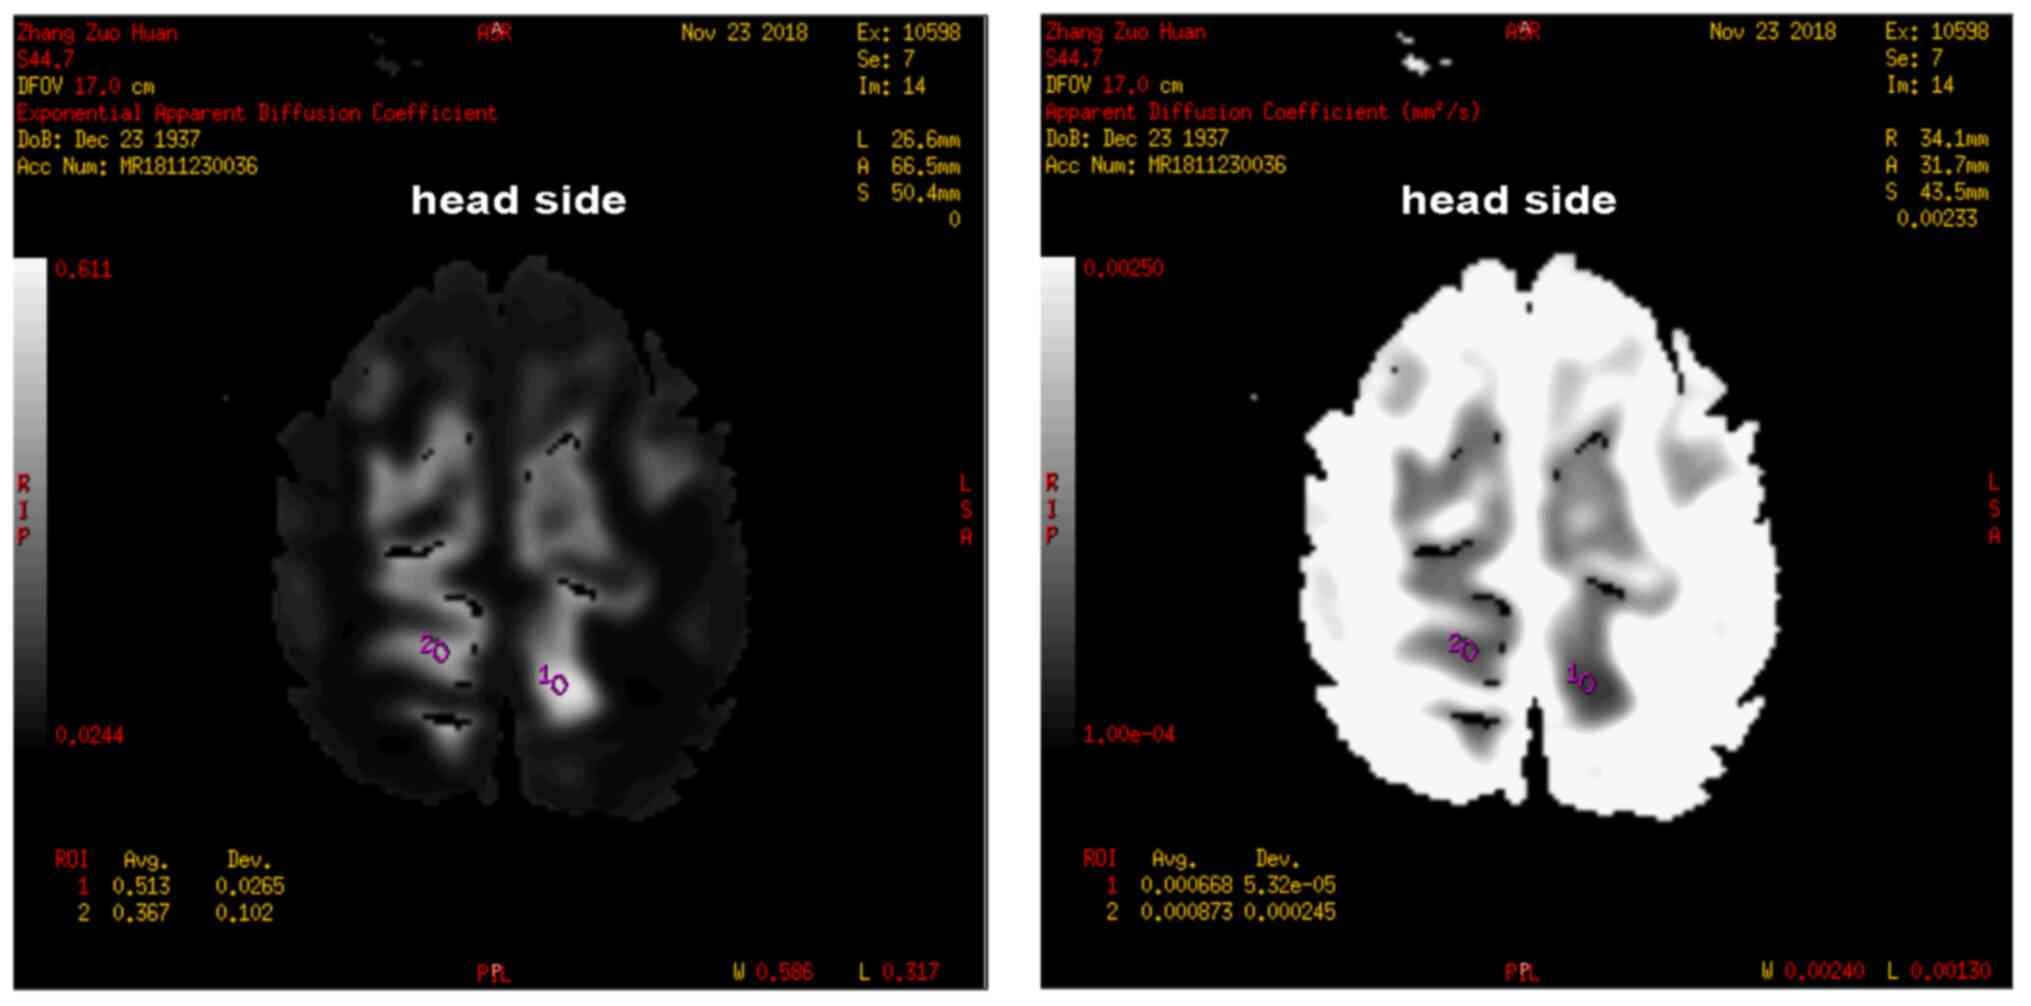

Diffusion-weighted magnetic resonance imaging revealed acute infarction in the left parietal lobe and magnetic resonance angiography detected stenosis of both posterior cerebral arteries (Fig. 1). No responsive stroke and associated symptoms were found.

Figure 1

Diffusion-weighted imaging and apparent diffusion coefficient on admission showed acute infarction in the right parietal lobe.